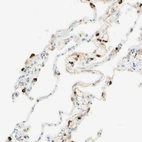

Immunohistochemical staining of human lung shows moderate to strong cytoplasmic positivity in macrophages.